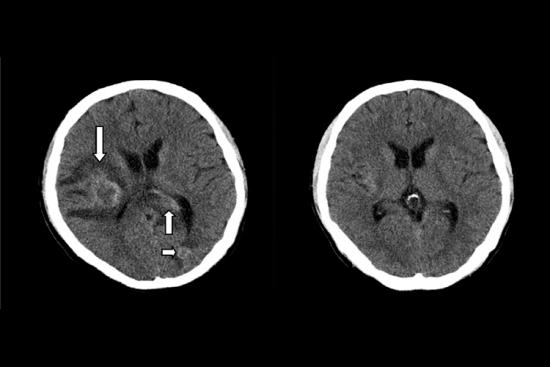

白血病患者可能存在出血倾向,出血点可能在机体任意部位,如皮肤表面可有出血点、瘀斑,口腔、鼻腔、消化道等部位黏膜也会有出血点。除此之外,内脏、颅内等也可能有出血,严重者可由于颅内出血而导致死亡。